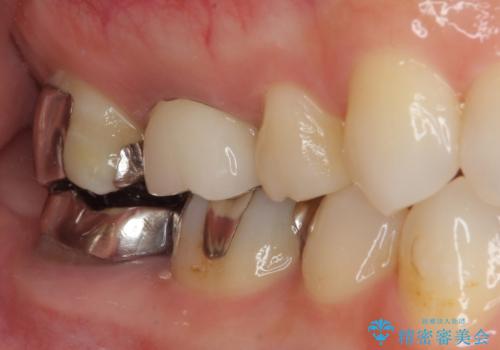

- 奥歯の金属の詰め物が取れたとのことで来院された患者様です。中学生の頃に根管治療を行い、そのあと金属の詰め物をいれていたそうです。

拡大鏡視野下で虫歯の除去を行い、オールセラミッククラウンに適した形に整えました。